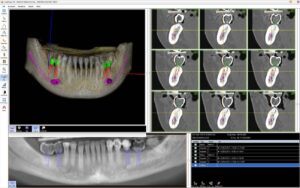

G) PROGETTAZIONE PER MEZZO DEL COMPUTER, CON LA RICOSTRUZIONE DIGITALE IN 3D DI ESAMI RADIOLOGICI E L’UTILIZZO DI MODELLI STEREOLITOGRAFICI.

Questa tecnologia ci permette di progettare e di stabilire a priori l’esatta posizione degli impianti da inserire, fig.45-46 evitare strutture anatomiche pericolose (nervi, arterie, muscoli ecc.) fig.46 di conoscere l’esatta morfologia dell’osso da utilizzare e le sue caratteristiche (densità trabecolatura ecc.);

inoltre ci consente di realizzare con precisione anche la protesi provvisoria immediata fig.47-48 prima dell’inserimento degli impianti. Questo manufatto così si adatterà perfettamente alla posizione dei monconi stabilita prima dell’intervento, in modo virtuale con il software 3D.

Da questo progetto virtuale eseguito sul computer è inoltre possibile realizzare (con l’utilizzo di una stampante 3D) un modello fisico (stereo-litografico) della mandibola o dell’osso mascellare riproducendo fedelmente tutti i dettagli anatomici. Su questo modello simuliamo le estrazioni dentali, le modifiche sull’osso

ed infine l’inserimento degli impianti valutando attentamente di non interferire con strutture anatomiche pericolose adiacenti. Tutto viene programmato e pianificato (misure e angolazioni impianti, innesti ossei, protesi provvisoria ecc.) PRIMA CHE VENGA RIPRODOTTO REALMENTE SULLA PERSONA CON L`INTERVENTO CHIRURGICO IMPLANTARE.